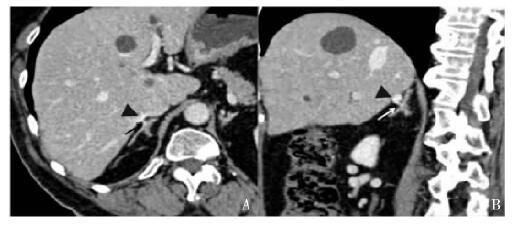

结果  以MIP或MPR技术评价图像质量, 左肾上腺静脉97例(97%)为1级, 1例(1%)为2级, 2例(2%)为3级; 右肾上腺静脉52例(52%)为1级, 19例(19%)为2级, 29(29%)例为3级。左肾上腺静脉均为1支; 91%与膈下静脉汇合后汇入左肾静脉; 左肾上腺静脉平均直径(3.6±0.6)mm(2.4~4.5 mm); 左肾上腺静脉与左肾静脉形成交角, 平均为(121.9±16.0)°(150~58°)。2例发现右侧双支肾上腺静脉; 67例(94%)右肾上腺静脉汇入下腔静脉, 4例(6%)汇入右副肝静脉; 右肾上腺静脉平均直径(3.2±0.5)mm(1.9~4.0 mm); 右肾上腺静脉与下腔静脉形成交角, 平均为(75.3±16.6)°(90~35°)。

Results  In the evaluation of image quality with MIP or MPR images, the left adrenal vein was excellent in 97% patients, sufficient in 1%, and non-diagnostic in 2%. For the right adrenal vein, 52% were excellent, 19% were sufficient, and 29% were non-diagnostic. The left adrenal vein was always a single one, 91% of which joined the inferior phrenic vein and then drained into the left renal vein. The diameter of the left adrenal vein ranged 2.4 mm to 4.5 mm (mean:3.6±0.6 mm). The angle of the left adrenal vein and left renal vein ranged 150° to 58° (mean:121.9±16.0°). Two patients were found to have double right adrenal veins. The right adrenal vein drained into the IVC in 67 of 71 patients (94%) and into the right accessory hepatic vein in 4 patients (6%). The average diameter of the right adrenal vein ranged 1.9 mm to 4.0 mm (mean:3.2±0.5 mm). The angle of the right adrenal vein and IVC ranged 90° to 35° (mean:75.3±16.6°).